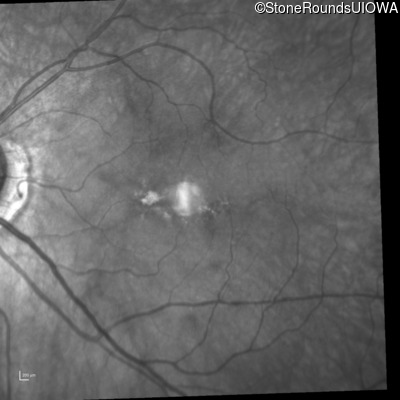

Infrared Fundus Photograph - Right - 20/200

Exemplar